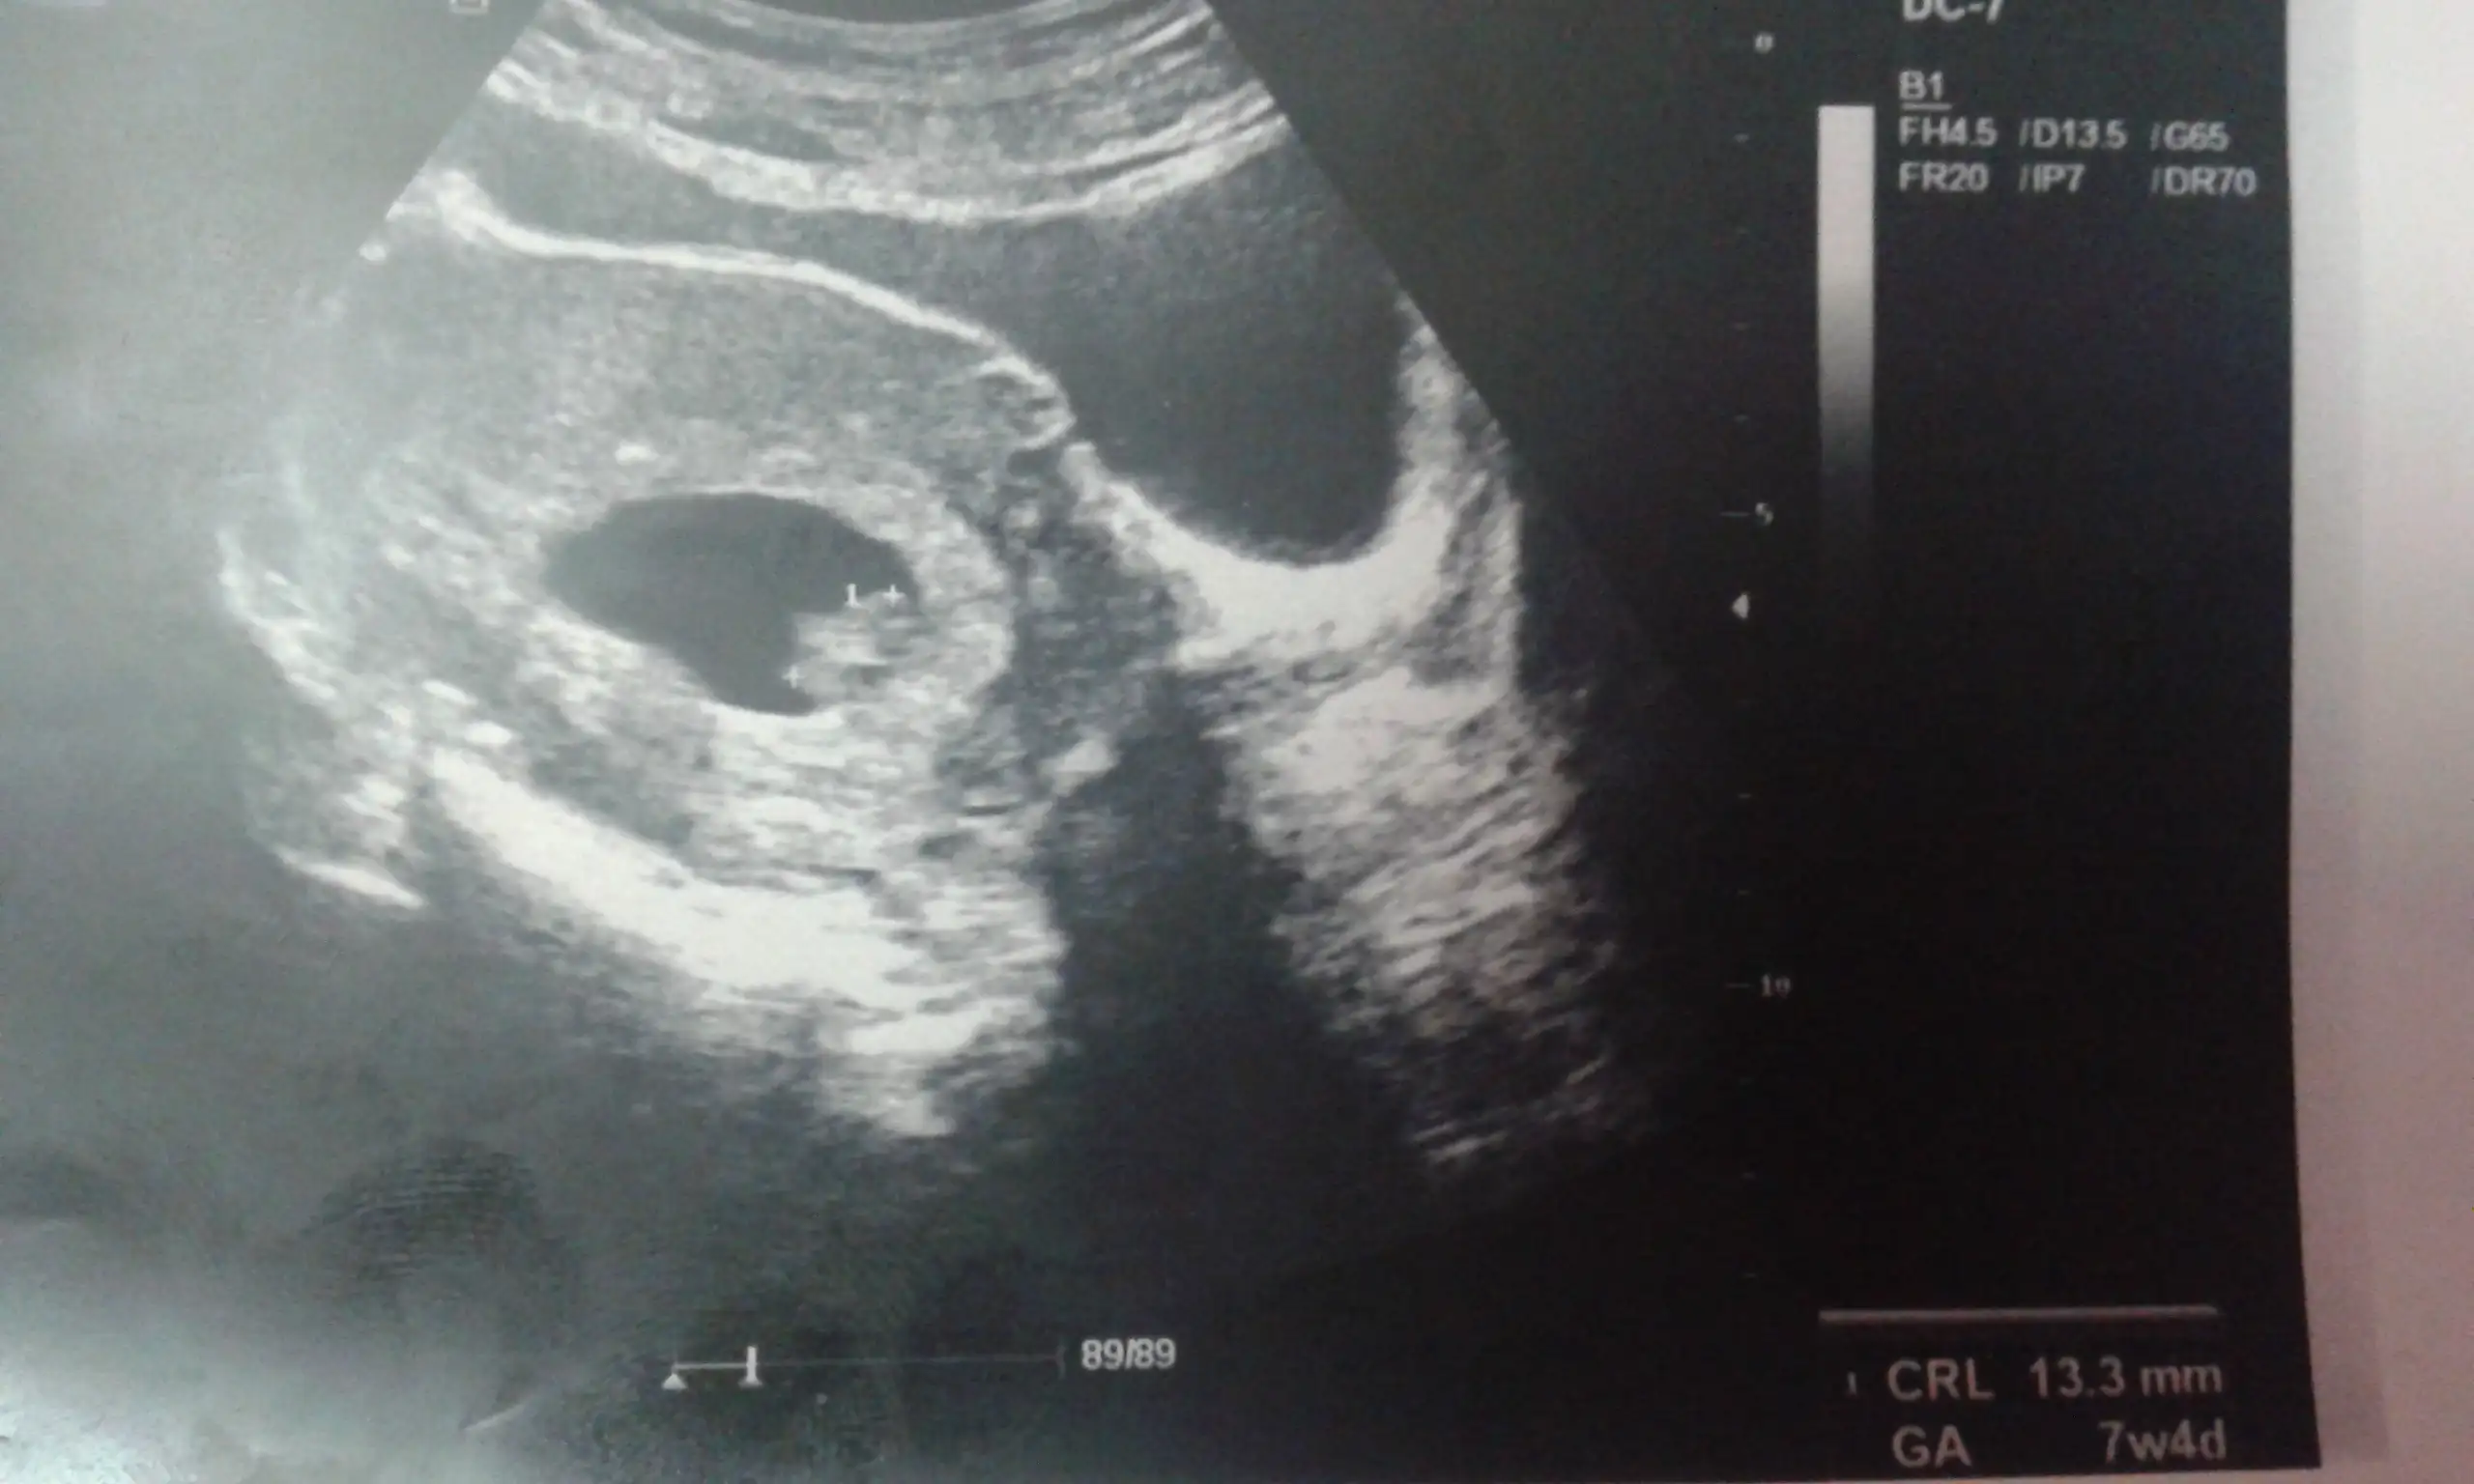

Kizlar benim bebisime de yorum yapar misiniz☺☺ 7+4 gunluguz burda

Eklentiler

• 20141120_223301.webp

70,4 KB · Görüntüleme: 195

cnm bende 7+4 te aynen böyleydi yarın tam 8 haftalık olacak usg aynı resim koyamadım direk bakınca bana göre sağ tarafta bebek galiba kafası da sağ tarafta tam seçemiyorum sürekli bakıyorum da :) acaba cinsiyeti ne bu durumda

Canim burdaki cogunluga gore galiba kız ☺ aslinda ben hep erkek hissediyodum ama bu ultrason goruntusunden sonra kiz gibi hissetmeye basladim insan ister istemez etkileniyor ☺